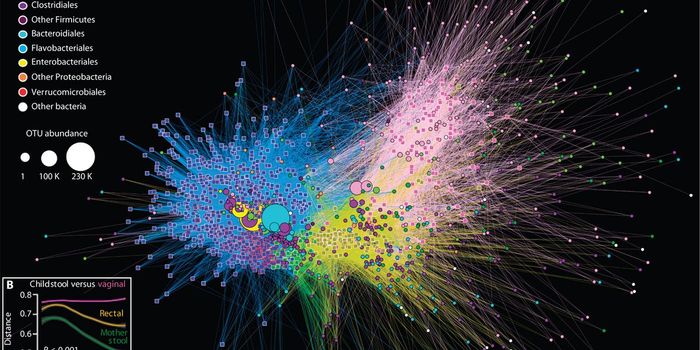

SEP 12, 2016MicrobiologyThe first month of a newborn’s life is so critical to a lifetime of health that this period has a name: neonate. I ...

MAR 04, 2019MicrobiologyThe foundations of our microbiome are laid very early, and can have a lifelong impact on our health.

JUN 18, 2016MicrobiologyIn a new issue, Science Translational Medicine presents two related papers that demonstrate variations in the gut microb ...